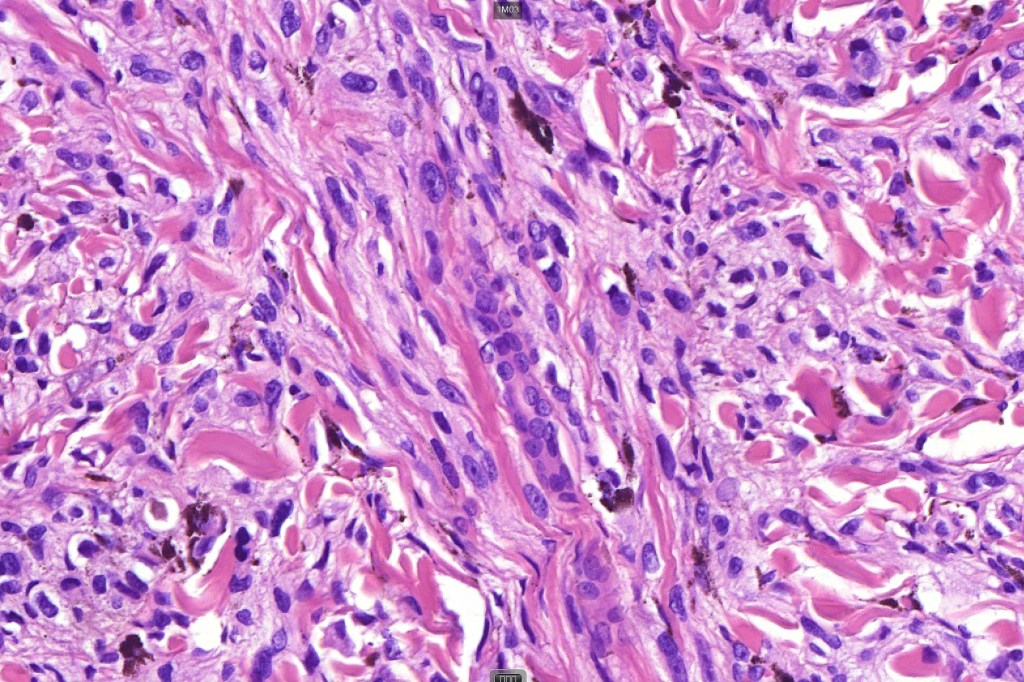

•Symmetrical, circumscribed wedge-shaped infiltrate-most common growth pattern with the broad base uppermost, deeper aspect extends along appendageal structures & neurovascular bundles with a fasciular or plexiform pattern

•Plexiform growth pattern very occasionally seen (plexiform spindle cell nevus (Barnhill)

•Superficial epithelioid cells

•Deep spindle cells